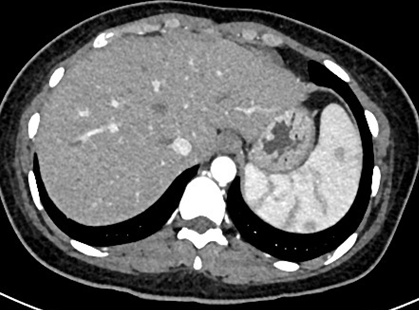

办好住院已经是1月13日下午四点了,介入科方淳主任及团队加班加点,当天晚上就为患者做了肠系膜动脉和静脉造影,结果没有发现大血管的问题,但是小血管充血、丰富,呈梳子样改变(称为“梳子征”,图1)。排除了肠系膜大血管的问题之后,高度怀疑肠系膜小血管炎可能,事不宜迟,赵家胜主任通过电话联系到风湿免疫科值夜班的王璇主治医生,王医生仔细询问了病史,了解到患者有过脱发和自发性流产的病史,结合本次肠道小血管炎的表现,高度怀疑系统性红斑狼疮引起的肠系膜血管炎。为了缓解患者的腹痛,挽救病人的生命,王璇医生基于对病情的判断,在化验结果尚未出来的情况下果断使用了糖皮质激素,第二天早上(1月14日)患者腹痛和恶心、呕吐即明显好转,患者胃口也开了,随后吃了点半流质,但下午又出现了腹痛和呕吐,这时化验结果也出来了(见图2),狼疮的标志性抗体-抗Sm抗体和ds-DNA抗体均阳性,证实了系统性红斑狼疮的诊断。赵主任和风湿免疫科汤建平主任共同查房后认为系统性红斑狼疮诊断明确,以急性腹痛起病,而且一发病就表现为狼疮危象的红斑狼疮少见,常规剂量激素疗效不佳,腹部CT结果显示肠壁水肿和胸腹水有进展(见图3、图4),需要立即进行大剂量激素冲击治疗。

图3. 1月15日CT肠壁增厚水肿(箭头所指)

图4. 治疗前胸腹水(箭头所示)

第四天(1月16日)患者病情即明显好转,到1月24日复查CT,肠壁水肿消退(见图5)、胸腹水完全吸收(见图6),患者腹痛缓解,已能正常进食。